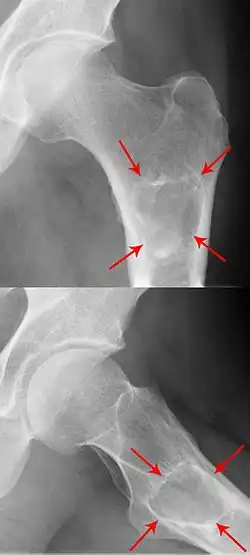

Röntgen

Im Röntgenbild stellt sich das klassische Enchondrom als zur Knochenachse längliche, ovaläre Läsion zentral im Markraum langer Röhrenknochen dar. Eine exzentrische Lage schließt ein Enchondrom jedoch nicht aus. Das Zentrum der Läsion liegt meist in der Metaphyse oder in der distalen Diaphyse eines Röhrenknochens. Ein kleiner oder kurzer Knochen kann vollständig ausgefüllt sein. Typisch für Enchondrome ist eine Ausdünnung der Kortikalis des Knochens von innen, das sogenannte Scalloping und im Falle einer Expansion über das Volumen des Knochens hinaus die Neubildung der Kortikalis (Neocortex). Eine Periostreaktion wird jedoch praktisch nie beobachtet. Das Erscheinungsbild eines Enchondroms wird des Weiteren hauptsächlich vom stark variierenden Ausmaß der Verkalkungen der primär knorpeligen Tumormatrix geprägt: diese können punktförmig, ring- und bogenförmig („rings and arcs“) und flockig sein. Oftmals imponiert das Bild Popcorn-artig. Die Verkalkungen treten häufiger und ausgeprägter in den langen Röhrenknochen auf, während die Läsionen in den kleineren Knochen der Finger und Füße weniger verkalken. Das Röntgen-Bild erfasst sicher nur die Verkalkungen und das Scalloping, so dass das wahre Ausmaß eines nur gering verkalkten Enchondroms mit dieser Methode unterschätzt werden kann. Verschwinden von vormals verkalkten Arealen innerhalb eines Enchondroms im Verlauf muss als Hinweis auf eine Entartung gedeutet werden.[2]